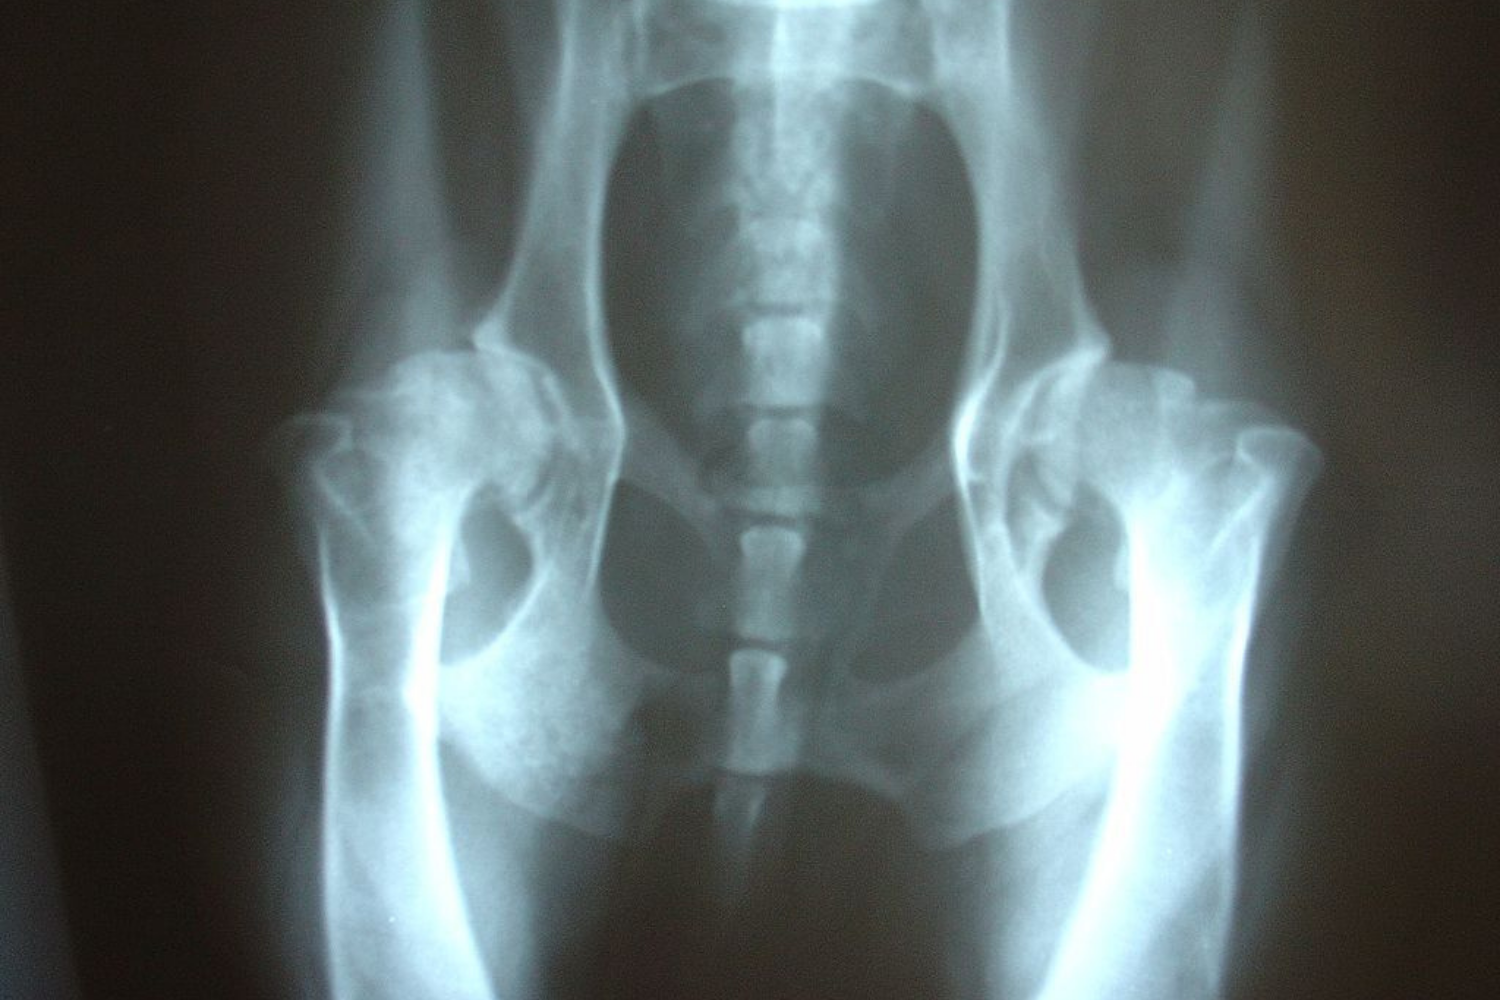

For a definitive or final OFA evaluation, you submit a single extended-view hip x-ray, which the OFA sends to a panel of three board-certified veterinary radiologists. These experts independently evaluate nine anatomical regions of the joint, looking for deviations consistent with hip dysplasia, such as structural abnormalities and laxity. OFA results are most predictive if the dog is 24 months or older when x-rayed. More on OFA hip evaluations here.

PennHIP uses three different radiographic views to measure the laxity of each hip joint. One of the views is the same as the OFA extended view so your vet can make two copies of this x-ray to submit to both organizations. The other two x-rays are carefully measured and result in the distraction index (DI). The higher a dog’s DI, the greater the risk of developing hip dysplasia. Dogs with scores of a 0.3 or LESS have a very low risk of hip dysplasia. Dogs with a DI of .7 or higher have an extremely high risk of hip dysplasia.